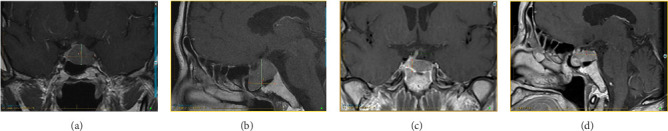

背景:促甲状腺激素(TSH)分泌型垂体腺瘤(TSHomas)是一种非常罕见的垂体肿瘤,可引起中枢性甲状腺功能亢进。大多数为大腺瘤(≥10mm),诊断时伴有局部和全身合并症。甲状腺功能试验(TFTs)的不典型变化可能是微妙的,最初常常被遗漏,而其他垂体激素的过度分泌往往存在。生长抑素类似物(SSAs)是推荐的一线药物治疗这些病变。我们报告两例TSHomas成功地管理与多巴胺激动剂(DA)治疗,单独或后经蝶窦手术(TSS)。病例介绍:一名47岁男性,表现为体重明显减轻、疲劳和肌肉无力。他被发现有高泌乳素血症、继发性肾上腺功能不全(AI)和中枢性性腺功能减退,导致发现一个3厘米的侵袭性垂体腺瘤。额外的测试显示IGF1, TSH和游离T4增加。经TSS部分切除后病理证实为Pit-1多激素肿瘤。持续的高催乳素血症和中枢性甲状腺功能亢进对DA治疗有反应,因为患者拒绝治疗。66岁男性,有焦虑、高血压、冠状动脉疾病、房颤、甲状腺结节病史,因严重头晕就诊,头部CT扫描发现垂体腺瘤2.4 cm。实验室记录显示,在过去的五年中,游离T4和TSH逐渐异常增加。他拒绝手术,对DA治疗有很好的临床和生化反应。结论:通过长期监测和正确解释TFT,及时发现中枢性甲状腺功能亢进,对tshoma的早期诊断和最佳治疗至关重要。分泌tsh的腺瘤可能对DA治疗有反应。

Background: Thyroid-stimulating hormone (TSH)-secreting pituitary adenomas (TSHomas) are very rare pituitary tumors causing central hyperthyroidism. Most are macroadenomas (≥ 10 mm) with local and systemic comorbidities at diagnosis. The atypical changes in thyroid function tests (TFTs) may be subtle and are often initially missed, while over-secretion of other pituitary hormones is often present. Somatostatin analogs (SSAs) are the recommended first-line medical therapy for these lesions. We report two cases of TSHomas successfully managed with a dopamine agonist (DA) therapy, alone or following transsphenoidal surgery (TSS). Case Presentation: A 47-year-old man presented with significant weight loss, fatigue, and muscle weakness. He was found to have hyperprolactinemia, secondary adrenal insufficiency (AI), and central hypogonadism, which led to the discovery of a 3 cm invasive pituitary adenoma. Additional tests showed an increased IGF1, TSH, and free T4. A Pit-1 multihormonal tumor was documented on pathology after partial resection by TSS. Persistent hyperprolactinemia and central hyperthyroidism responded to DA therapy, as the patient refused therapy. A 66-year-old man with a history of anxiety, hypertension, coronary artery disease, atrial fibrillation, and thyroid nodules, was consulted for severe dizziness and was found to have a 2.4 cm pituitary adenoma on a head CT scan. Lab records showed a progressive supranormal free T4 and TSH increase over the preceding five years. He refused surgery and had an excellent clinical and biochemical response to DA treatment. Conclusion: Prompt detection of central hyperthyroidism by monitoring and correctly interpreting TFT over time is essential for early diagnosis and optimal management of TSHomas. TSH-secreting adenomas may respond to DA therapy.